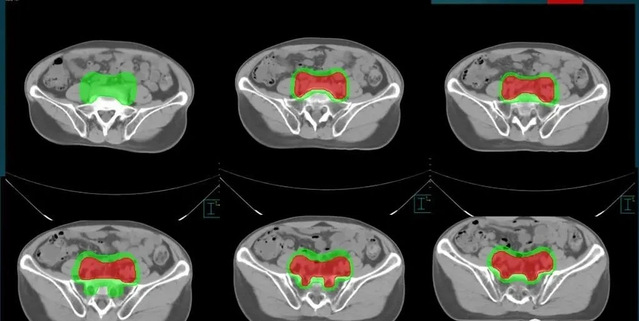

放疗医生在模拟定位过程获得的CT图像上逐层(30-80层)勾画患者的肿瘤及需要照射的区域,同时还需要勾画出需要保护的正常器官(10-30种)。靶区的确定和放疗剂量、照射次数都有关系,还需要考虑到正常器官。

直肠癌靶区勾画示例